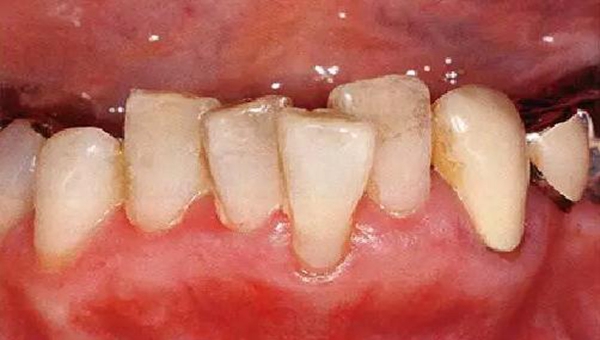

●33歲男性 侵襲性牙周炎廣泛型口腔內(nèi)照片

33歲男性,吸煙(1天10根,12年吸煙史)。菌斑控制狀況不好,牙周探診全頜牙周袋深5~10mm之外,全頜性牙周袋出血,部分牙周袋有排膿現(xiàn)象。X片可觀察到全頜性重度骨吸收。通過(guò)以上檢查可診斷出該患者為侵襲性牙周炎廣泛型。視診可知牙齦雖然有炎癥,但沒(méi)有出現(xiàn)嚴(yán)重浮腫,沒(méi)有大量牙結(jié)石沉積。